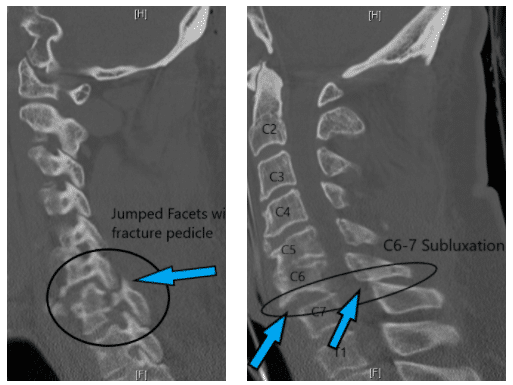

An urgent CT scan was performed which showed Cervical Spine injury with unilateral facet dislocation of C6-7 on the right side with fracture of the pedicle along with sublxation of C6 over C7 vertebra.

C6 over C7 vertibrae

Jumped Facets Right Side

The facet dislocation was causing compression of the spinal cord at the neck level and the patient had an incomplete neurological deficit. He needed urgent surgery to remove the compression of the spinal cord.